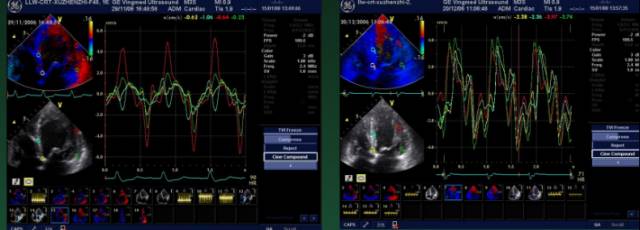

组织多普勒超声在CRT参数优化中的应用

将左室分成12个节段,分别测量QRS起点距左室各节段收缩速度峰值的时间,(Ts),其标准差即为左室内不同步指数(Ts-SD)